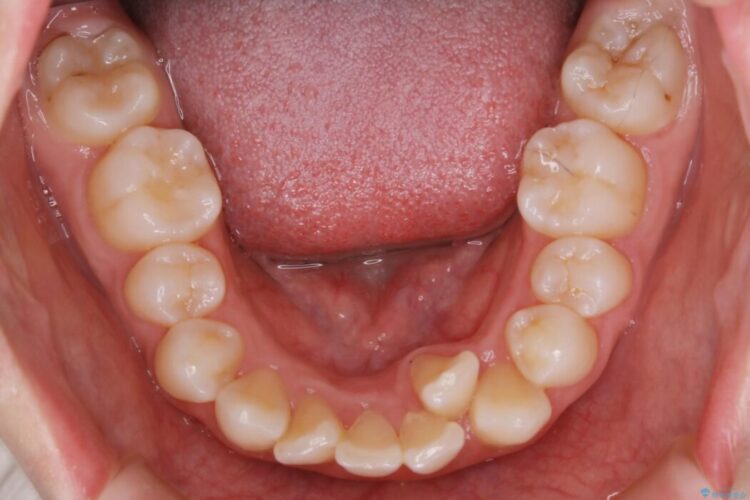

検査したところ歯に対して骨が上顎・下顎共に小さいことがわかりました。

それによりスペースが少なく歯列がガタついたり前方傾斜する生え方となっていました。

よって本症例では抜歯により歯の本数を減らすことにより整えるスペースを確保してワイヤー装置にて歯列矯正を行うこととしました。

本症例の患者様は顎の骨が小さく歯をきれいに並べるための隙間がないため、歯が重なったり傾斜してしまっていました。

抜歯を行うことによりスペースを確保し、小さい骨幅でも歯並びを整えることができます。